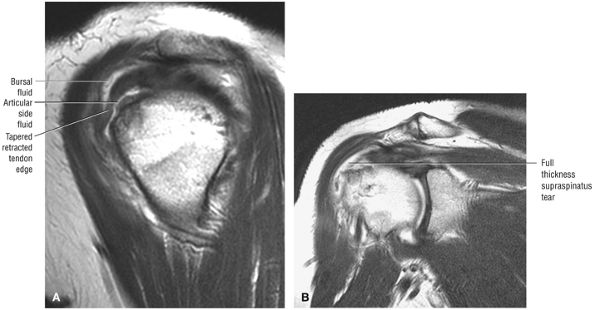

FIGURE 8.102 ● (A) The anterior undersurface of the acromion and the coracoacromial ligament form the coracoacromial arch. The subacromial subdeltoid bursa facilitates the passage of the rotator cuff and proximal humerus under the coracoacromial arch. (B) A superior axial image shows the anterior-to-posterior extent of the coracoacromial (CA) ligament perpendicular to the supraspinatus tendon. The fluid in the subacromial-subdeltoid bursa represents fluid between two serosal surfaces in contact with each other. One serosal surface is contributed by the undersurface of the coracoacromial arch and deltoid, and the other serosal surface is on the bursal side of the cuff.

|

![]() |